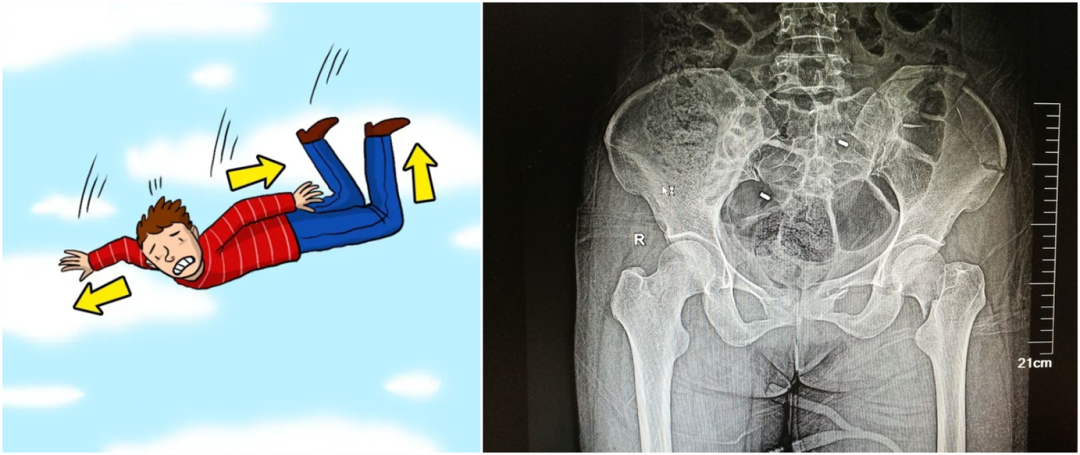

從暴力的大小來看,還可以細分為高能量的損傷和低能量的損傷。比如說,如果是車子撞的,從高處墜落,通常會造成高能量的損傷,而普通的跌倒造成的骨折,一般不太嚴重,可以說是低能量的損傷。

外傷性骨折

【醫療科普】:外傷性骨折影像